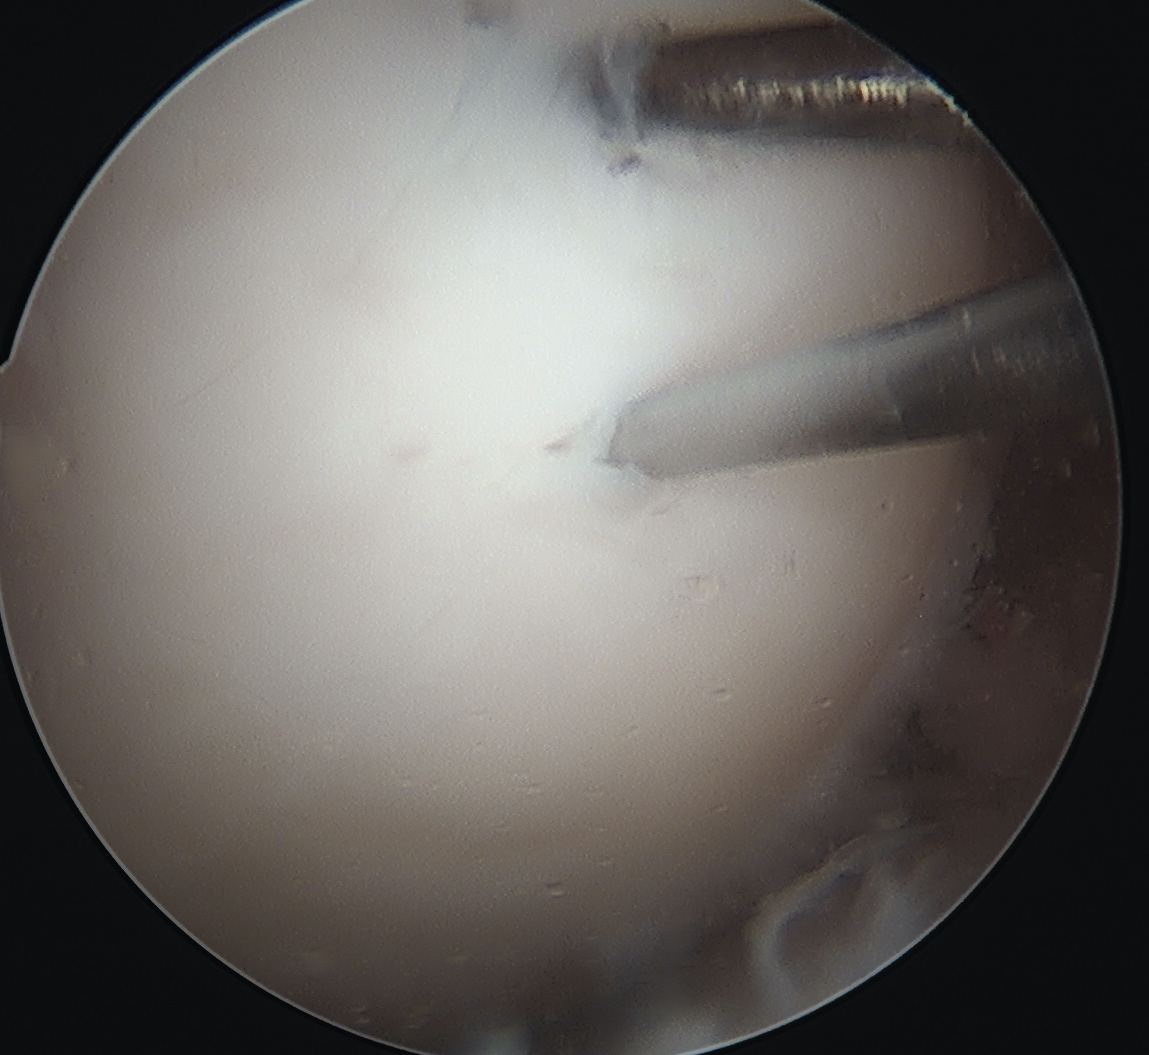

- can microfracture with 1 mm k wire around screws

- ensure K wires centered in fragment

- can microfracture around screws